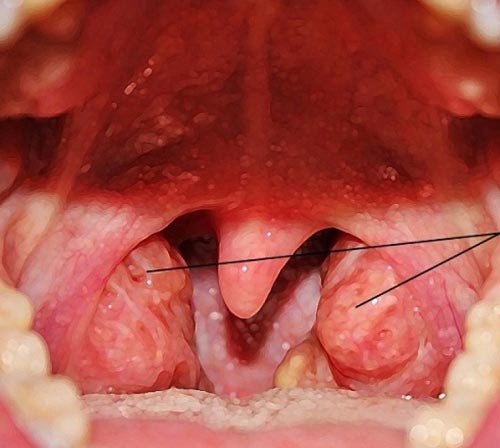

Затруднение носового дыхания связано с механическим препятствием. Выглядят аденоиды увеличенными, отечными, слизистая становится красной. Они полностью не закрывают просвет носоглотки при начальной стадии развития.

Иногда распознать аденоиды можно уже по одному признаку – отсутствие свободного дыхания через нос.

У детей формируется узнаваемое аденоидное лицо. Рот постоянно полуоткрыт, носогубные складки сглажены, нижняя челюсть отвисает. Аденоидные вегетации нарушают нормальный процесс формирования зубов и скелета лица. При этом резцы развиваются неправильно, аномальный прикус и искривленная носовая перегородка. Беспокоит кашель.

В зависимости от выраженности симптомов заболевания и степени сужения просвета в носоглотке используется 2 подхода — лечение аденоидов у детей без операции или их удаление (смотрите аденоиды на фото). Наиболее безопасным способом является удаление аденоидов лазером. Предлагают лечить детей оперативно только при отсутствии эффекта от консервативной терапии. Оно считается наиболее предпочтительным. Всегда существовала проблема – удалять или нет разросшиеся аденоиды.